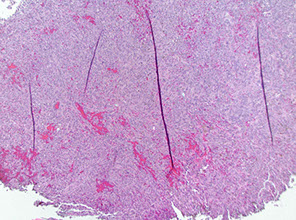

Temporal (Giant cell) aortitis/arteritis

Micro: Fragmented elastic fibers, giant cell / granulomatous (macros and lymphos) response and intimal thickening which reduces lumen

- giant cells not required for temporal arteritis (in ~75%), only destruction of internal elastica with inflammation

Giant cell arteritis of the breast. The vessel wall has been replaced by granulomatous inflammation. The process has compressed the vessel lumen to near-complete obstruction. A giant cell is shown in this field. B, Giant cell arteritis of the breast. Granulomatous inflammation and fibrinoid necrosis are shown within the wall of this vessel. C, Giant cell arteritis of the breast. The special elastin stain highlights the fragmentation of the internal elastic

lamina in this vessel (hematoxylin-eosin, original magnifications320 [A and B]; original magnification320 [C]).